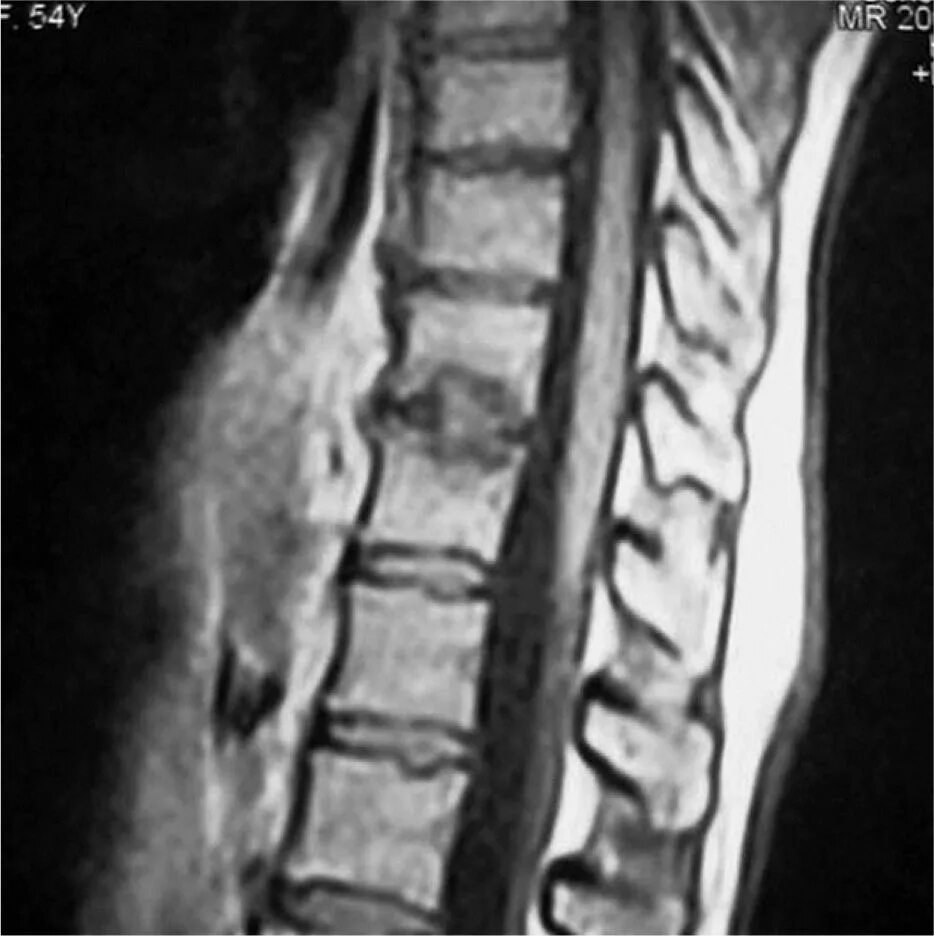

Узлы шморля в грудном отделе что это